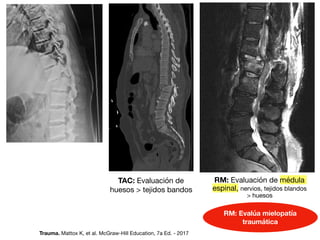

Fx: fractura

TAC: Evaluación de

huesos  tejidos bandos

RM: Evaluación de médula

espinal, nervios, tejidos blandos

huesos

RM: Evalúa mielopatía

traumática

Trauma. Mattox K, et al. McGraw-Hill Education, 7a Ed. - 2017